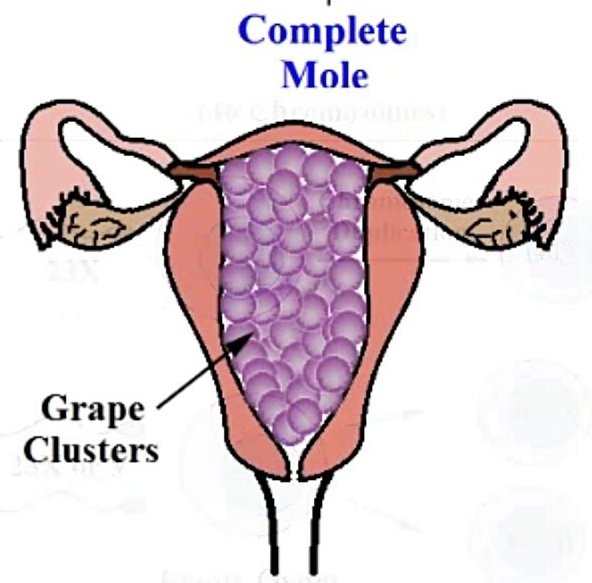

Медицина и диагностика: Инвазивный пузырный занос на УЗИ